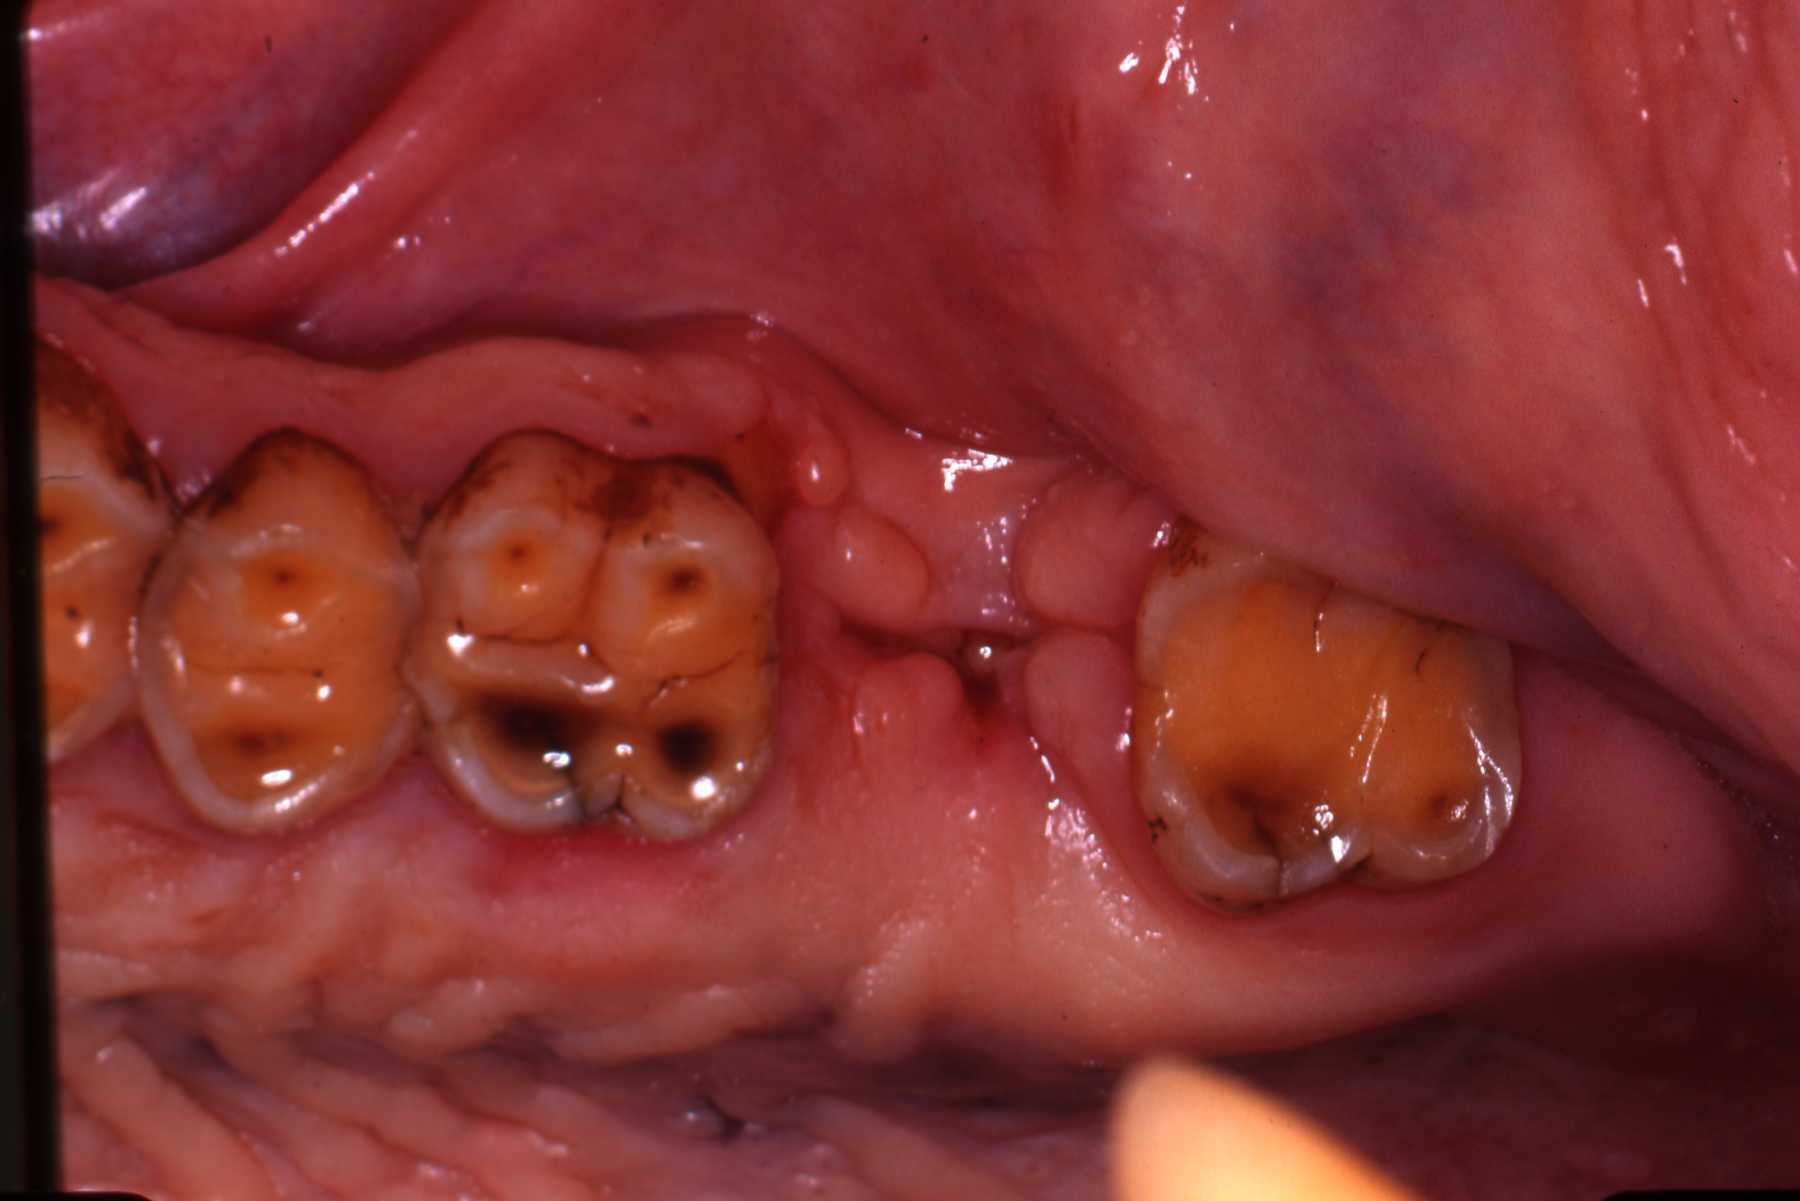

Bonobo Ricky with fractured central incisor. Endodontic therapy, composite resin restoration. Supernumerary maxillary right premolar. The supernumerary caused root resorption of no. 105. 105 was also extracted.

We have also encountered anatomic variations and anomalies in several species such as supernumerary teeth and impactions. Again, knowing the "normal" situation and always taking preoperative radiographs is necessary to recognize such situations. Such variations and anomalies do not necessarily warrant treatment unless they are causing or will very likely lead to pathosis.